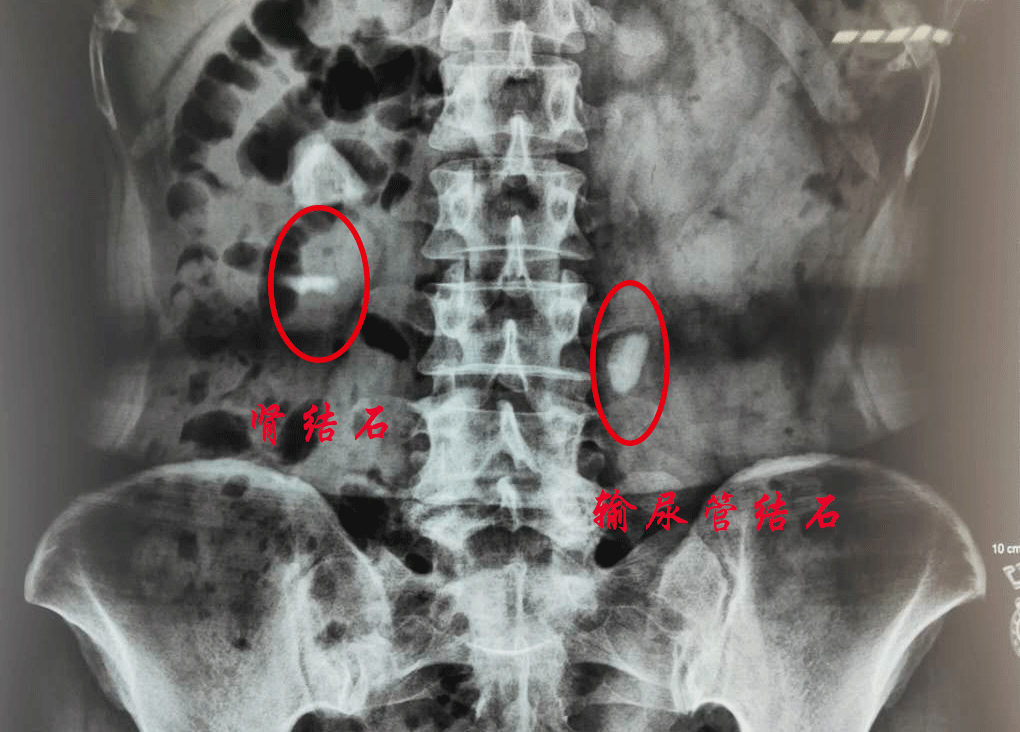

泌尿系结石包括肾结石、输尿管结石、膀胱结石和尿道结石。不同部位的结石有不同的症状。最主要的症状可以概括为四点:腰部胀痛、血尿、呕吐、发热等。